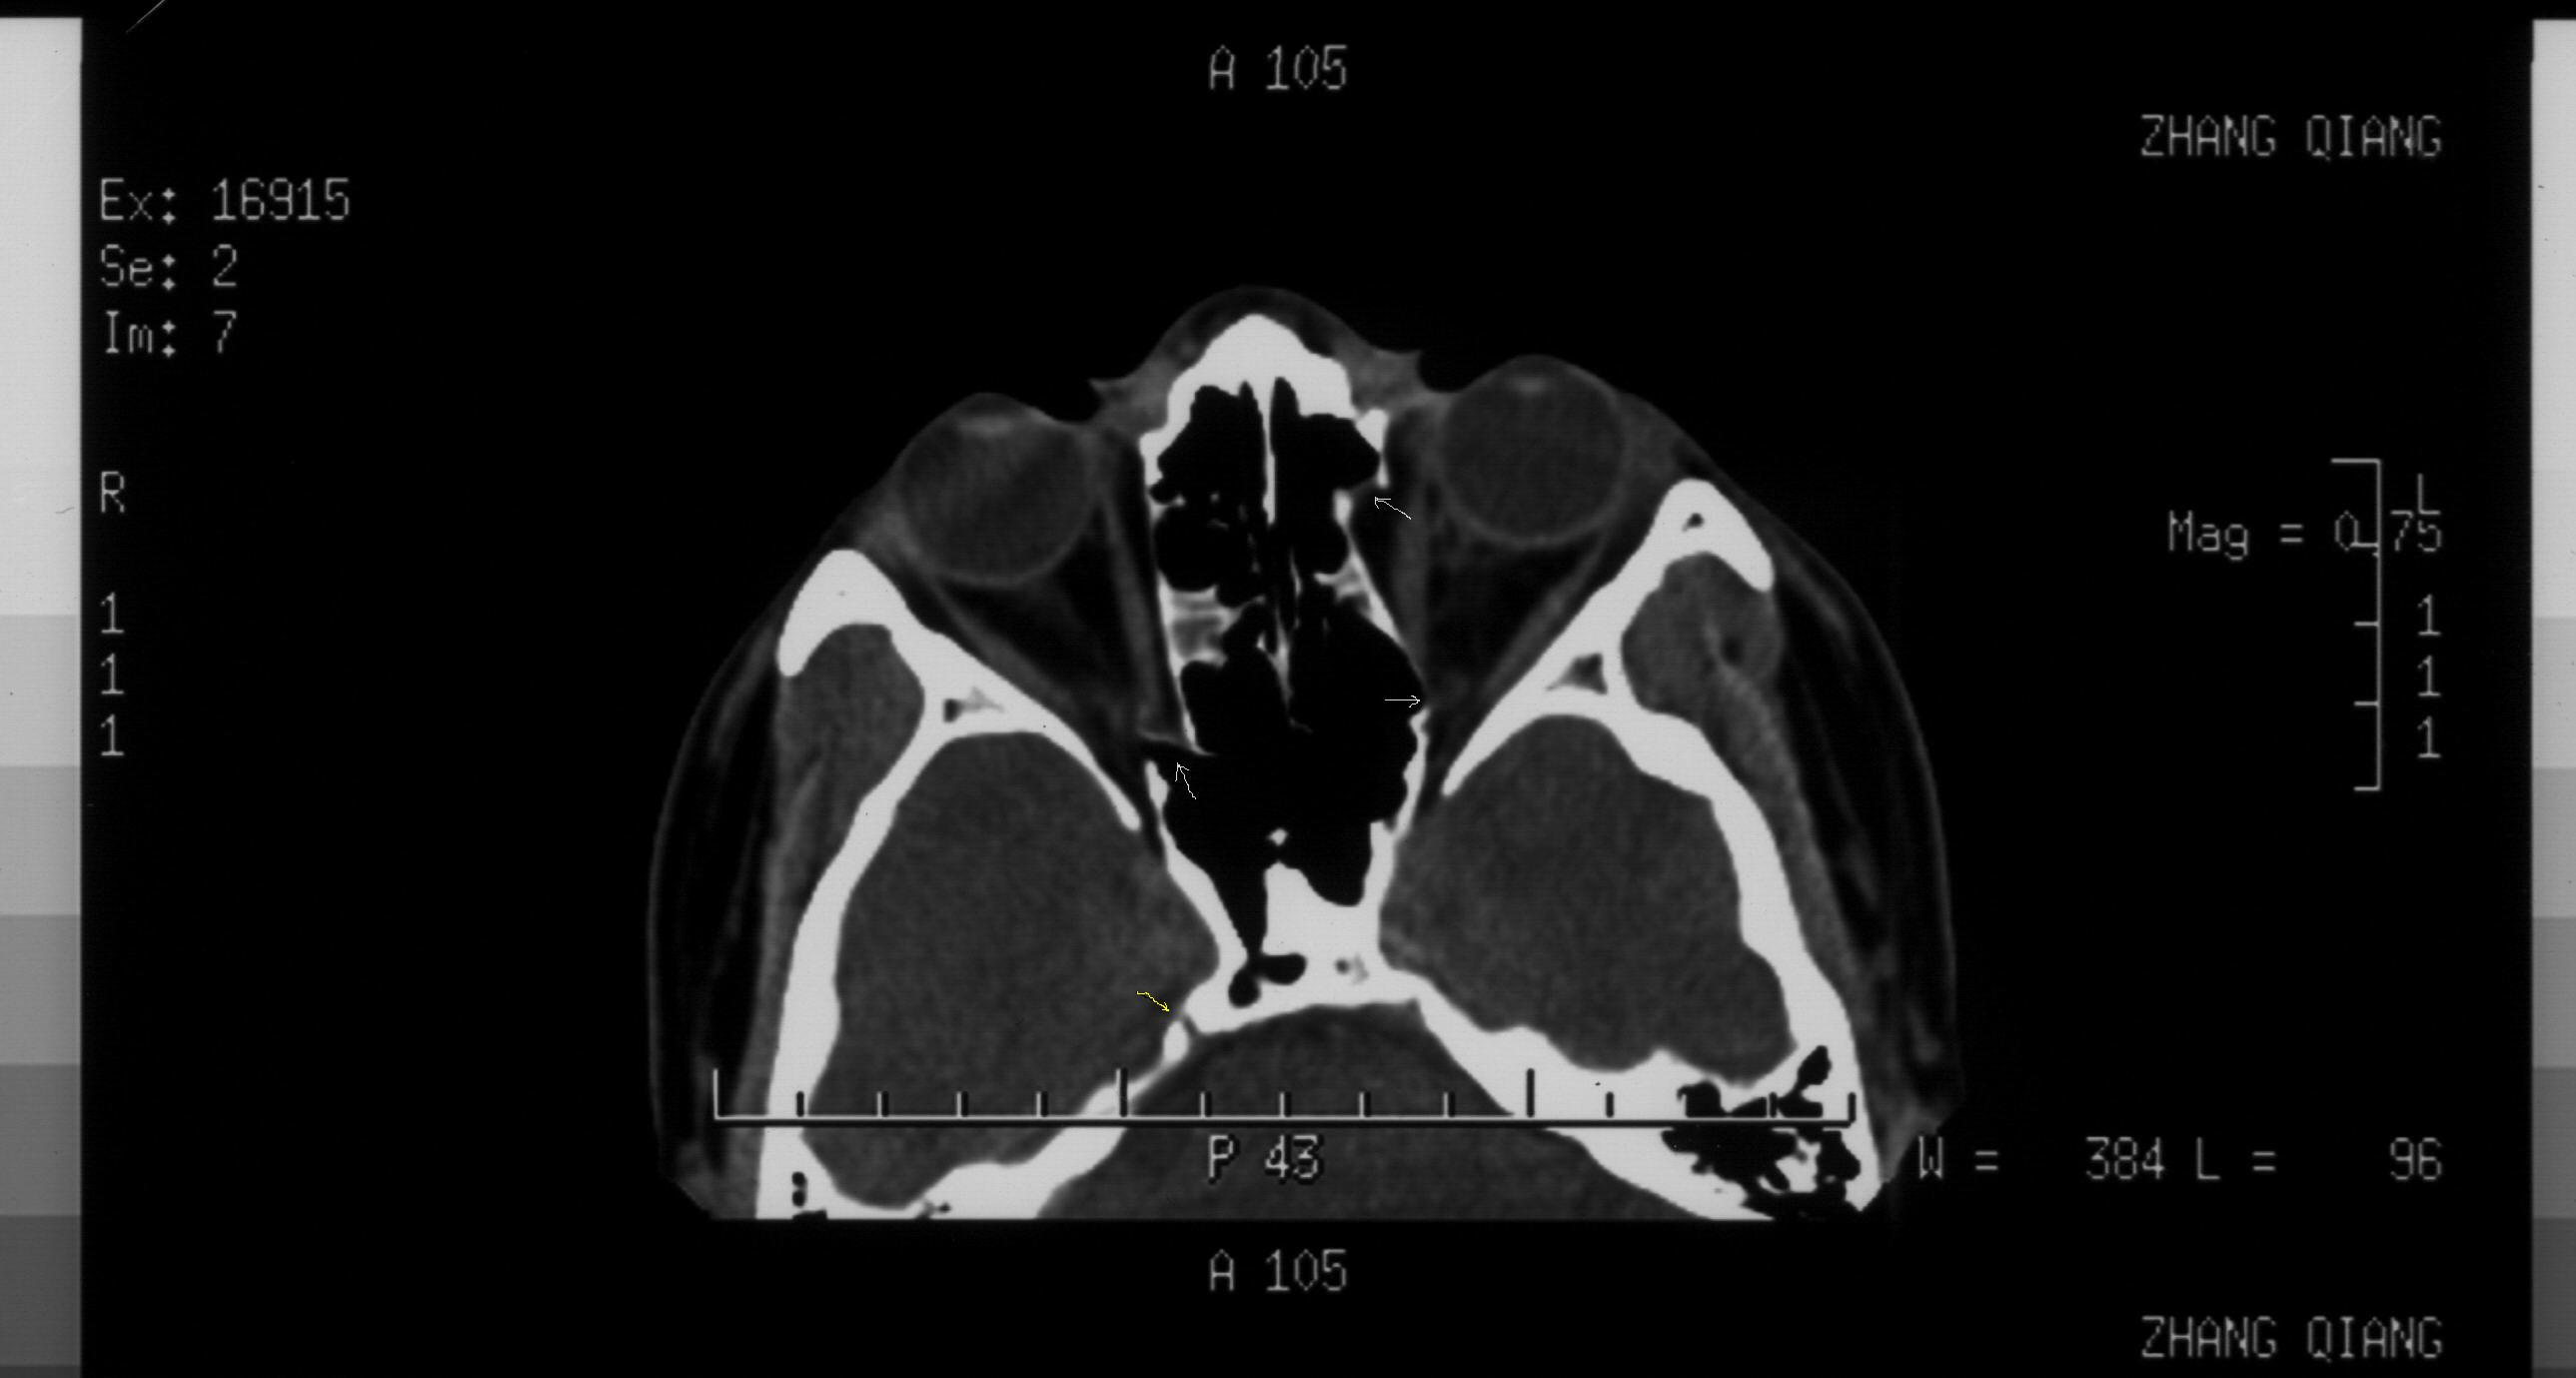

图588:可以看到箭头所示双侧纸样板骨折、移位。右侧骨折部位靠近眶尖,需要注意以下问题:1、通过视神经管薄层扫描除外视神经管骨折(结合临床视力和瞳孔反射)2、调出软组织窗,本人高度怀疑有内直肌近腱环处撕裂伤抑或是合并嵌顿。如同所述,则是急诊手术的绝对适应症,不能延误。左侧前部纸样板骨折明确,内直肌并未嵌顿在此处。而后部为可以骨折,希望结合上下层面及临床考虑,处理原则同前述。顺便提一下,右侧岩锥可疑裂缝,虽不能完全除外骨折,不过本人觉得正常骨缝的可能性更大。根据影像学经验,一般颅骨线状骨折的裂缝比较细小。另外,如果该部位出现骨折,则伴随临近部位的组织损伤和功能损害,果真如此,那就麻烦大了:首先,从神经科角度,颞叶出血、水肿或者该处脑膜下积血都会很严重。而此处又比邻海绵窦,可能的情况不用说了。第3、我们知道外展神经是颅内走行最长的颅神经。而在这个部位的解剖特点是边缘锐利,外展神经经此爬行,若发生外伤很容易伤及神经。所以,你要是真的想进一步了解这个区域,建议你行颅底薄扫加MRI。你自己权衡吧。

图560:箭头所示左侧鼻骨及鼻中隔骨折明确。另外,对于眼科医生应同时关注鼻泪管。通常这个部位容易被放射科大夫所忽视。